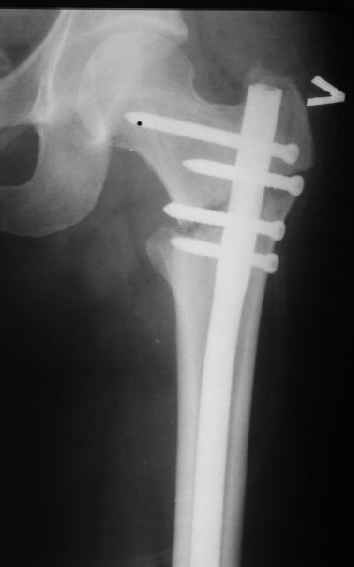

Картинка красивая, но на мой взгляд, не совсем оптимальная: Слишком медиально введён стержень - риск аваскулярного некроза головки бедра.

вариант межфрагментарного шинирования - зона достаточно простительная т.е. чрезвертельные переломы потенциально хорошо срастаются при любом

расположении сопредельных отломков- хорошая локальная васкуляризация. В приведённом случае я бы предпочёл принцип межфрагментарной компрессии (рекон/гамма нэйл 130- 135) принципу шинирования перелома.

Поясни, пожалуйста, почему решил шинировать косой чрезвертельный перелом?

Женя, эта картинка показывает не оптимальное лечение вертельных переломов в моем представлении, а особенности дизайна упомяутого фиксатора.

В частности, его возможности при фиксации переломов проксимального отдела бедра - в сравнении с другими, имеюшими лишь по одному статическому и динамическому отверстию и с кондуктором для введения 2 винтов.

Это было года 2,5 назад, мы тогда еще уточняли возможности шинирования с угловой стабильностью гвоздем с поперечным расположением винтов при переломах проксимального отдела бедра. Пациенту не пришлось приобретать намного более дорогой рекон или проксимальный гвоздь. В приложении еще несколько примеров применения того гвоздя при высоких переломах бедра, в том числе с более латеральной точкой входа. Гвоздь изгибаем для этого.